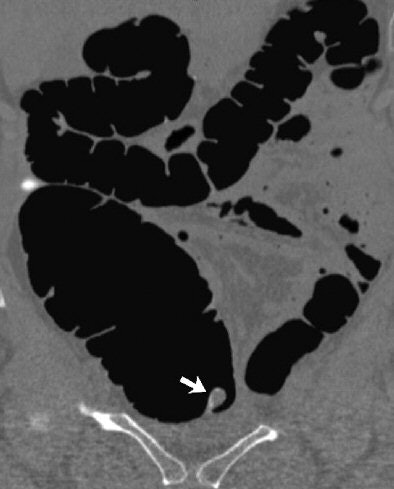

| Inverted appendiceal stump in 63-year-old asymptomatic woman. Coronal (C) 2D images from CTC confirm pedunculated lesion (arrow) detected on 3D view and show its soft-tissue composition. Image republished with permission of the American Roentgen Ray Society (AJR 2006; 186:535-538). |

The patient described above was referred for routine colorectal screening with VC. Her surgical history was significant only for remote appendectomy. She underwent standard bowel preparation of oral sodium phosphate (45 mL), 2% barium sulfate suspension (250 mL), and water-soluble iodinated contrast material (diatrizoate, 60 mL) the day before the exam.

Supine and prone CT images were acquired on a MDCT scanner (LightSpeed Ultra, GE Healthcare, Chalfont St. Giles, U.K.) using an 8 x 1.25 detector configuration, 1-mm reconstruction interval, 120 kVp, and 50 mAs. The study was interpreted by an experienced gastrointestinal radiologist using V3D Colon software (Viatronix, Stony Brook, NY). Primary 3D interpretation with 2D correlation of suspicious findings was used to interpret the results.

CT findings revealed a 10-mm pedunculated polypoid lesion at the medial base of the cecum. No additional findings were identified, but despite the surgical history and location of the lesion, "a neoplastic polyp could not be confidently excluded," the authors wrote. The patient was referred for conventional colonoscopy, which was negative.

"The endoscopic appearance of the polypoid cecal lesion was thought to be most compatible with an inverted appendiceal stump," the authors wrote. Biopsies revealed benign colonic mucosa with underlying lymphoid tissue.